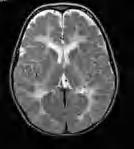

twarzy i obwodowych części kończyn. W postaci klasycznej, oprócz opóźnienia ruchowego i ataksji, w różnym okresie – po miesiącach, a nawet latach – dochodzi do rozwoju spastyczności. Obserwuje się ponadto elementy zespołu pozapiramidowego – u młodszych dzieci ruchy mimowolne, u starszych – dystonię. Rozwój umysłowy jest różny – od prawidłowego do niepełnosprawności intelektualnej w stopniu głębokim. Na ogół wzrok jest długo zachowany, mimo cech zaniku nerwów wzrokowych w badaniu dna oka. RM mózgowia ujawnia rozległą hipomielinizację istoty białej mózgu (z zajęciem torebek wewnętrznych, zwłaszcza odnóg tylnych), pnia mózgu i móżdżku – zmiany hiperintensywne w sekwencjach T2-zależnych (ryc. 5.1). U matek nosicielek istota biała może być niehomogennie zmieniona, z nieostrą granicą między korą a istotą białą.

Rycina 5.1. Choroba Pelizaeusa Merzbachera u 2-letniego chłopca. Niezmielinizowana, lekko hiperintensywna cała istota biała łącznie z torebkami wewnętrznymi. RM sekwencja T2-zależna.